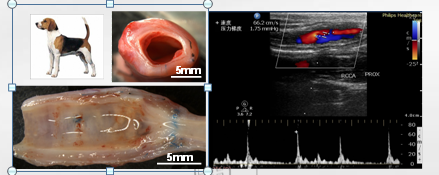

•CS-B-NO水凝胶通过增强Keap1的s-亚硝基化激活Nrf2信号通路,对缺血再灌注诱导的氧化应激导致的损伤心肌发挥保护作用,恢复氧化还原平衡;同时抑制NF-κB信号通路的激活及其下游促炎因子的表达,进一步调节心肌缺血/再灌注损伤后的炎症反应。

•本成果水凝胶可注射

•响应H2O2释放NO,实现NO靶向可控释放

•通过清除ROS和释放NO的双重功能,调节I/R损伤后ROS/NO失衡,治疗心肌损伤

心肌梗死的临床治疗主要通过恢复缺血心肌的血液再灌注来实现,心肌缺血/再灌注损伤导致线粒体中ROS明显过剩,与此同时,NO代谢发生改变,线粒体内NO和O2·− 严重失衡。

过量的ROS产生会与NO发生反应,导致NO的生物利用度降低。过氧亚硝酸盐的形成和相关蛋白酪氨酸硝化增加会对缺血心肌造成进一步损伤。本成果提供了一种可注射双功能水凝胶通过调节ROS/NO失衡治疗心肌缺血再灌注损伤。